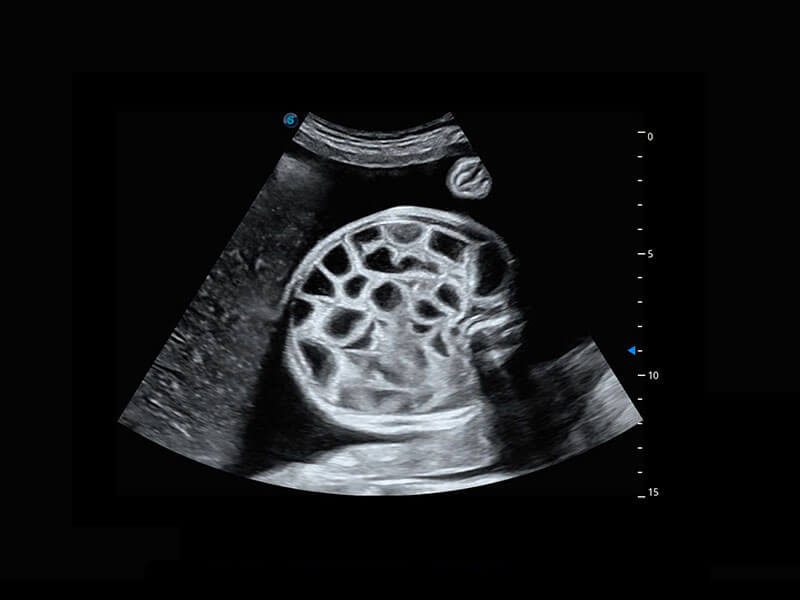

腔内三维-宫内节育器

高分辨率容积成像-早孕胎儿